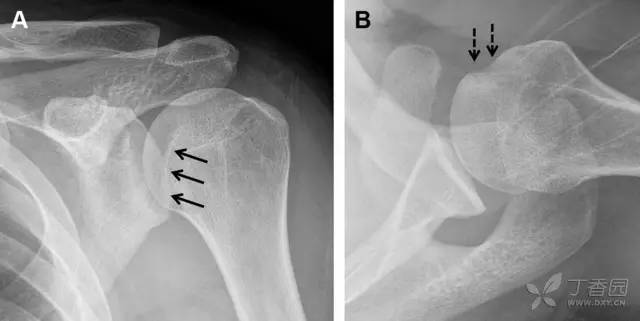

胫骨平台内侧皮质骨撕脱性骨折,被称为内侧 Segond 骨折或反向 Segond 骨折(图 5)。这种骨折的旋转机制与 Segond 骨折相反,该骨折与后交叉韧带断裂及内侧半月板损伤相关。

图 5 一位足球运动员的反向 Segond 骨折

A 正位片示关节线处的胫骨内侧见一细小骨折片(箭头)。B MRI 冠状位 T1 加权像示骨折片出现在内侧副韧带关节囊附着处(方框)。

为胫骨前内侧受到直接*力暴**作用,发生在腓骨茎突的横形骨折,可表现为弓形信号(图 6)。可伴发前交叉韧带或后交叉韧带的断裂。如果弓形信号被忽视或未处理,前交叉韧带的重建将失败。

图 6 跌倒后发生腓骨茎突骨折

A MRI 冠状位 T1 加权像示腓骨茎突撕脱性骨折(箭头)。弓状韧带附着于骨折碎片,而联合腱绕过外侧附着于其上。B 正位片见横形骨折线(箭头)。

约 6% 的后交叉韧带断裂与撕脱性骨折有关。X 线片特征表现为膝关节侧位片上可见大小不等的三角形骨折碎片移位到关节内(图 7)。

图 7 车祸后的后交叉韧带撕脱骨折

A 侧位片示后关节间隙见一移位的三角形骨折碎片(箭头)。B 矢状位 MRI 图像示骨折碎片(实箭头)附着于后交叉韧带上(空箭头)。

膝关节外侧由髂胫束、股二头肌和肌腱、外侧关节囊韧带及外侧副韧带组成。外侧副韧带对抗过度内旋*力暴**,维持膝关节稳定。当内旋*力暴**足够大时,韧带断裂或腓骨头撕脱性骨折就发生了。在 X 线片上,骨折线垂直于股骨头外侧(图 8)。

图 8 过度伸展引起的腓骨头撕脱性骨折

A 侧位片示腓骨头外侧的垂直骨折(箭头)。B MRI 冠状位 T1 加权像示骨折碎片同时附着于外侧副韧带(箭头)和弓状韧带上(弧形箭头)。